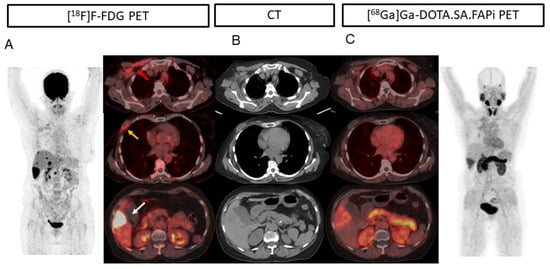

2. Results

2.2. Patient-Based Detection Rate Analysis

2.3. Lesion-Based Analysis

2.4. Comparison of Uptake and TBRs in Tumor Lesions